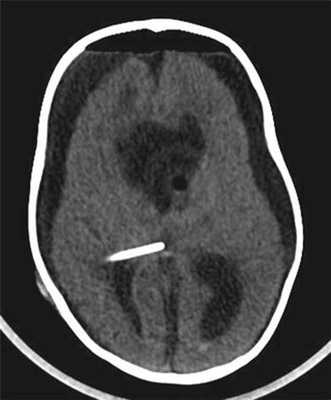

После проведенной интенсивной терапии и стабилизации состояния ребенка для уточнения степени кровоснабженности опухоли была произведена тотальная ангиография сосудов головного мозга — сосудистой сети опухоли не выявлено, дислокация сосудов мозга по гидроцефальному типу (рис. 3).

![]()

Рисунок 3. Тотальная церебральная ангиография сосудов головного мозга у грудного ребенка 11 мес c гигантской внутрижелудочковой опухолью. Сосудистой сети опухоли не выявлено, дислокация сосудов мозга по гидроцефальному типу (a — справа; б — слева).